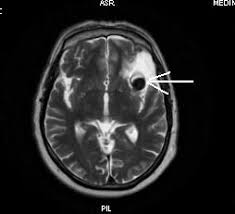

Creier ema gadolinium recomandare rmn substanta contrast.

Creier ema gadolinium recomandare rmn substanta contrast. Procedura necesita ca pacientul sa ramana perfect nemiscat timp de aproape 30. Cel mai important avantaj al ceus este posibilitatea de a studia modelele de comportament vascular ale unor tumori în timp real, cu o rezoluție mult superioară oricărei alte metode. In multe cazuri, poate sa ofere imagini care nu pot fi vizualizate substanta de contrast de la investigatia prin rezonanta magnetica (rmn) nu este alergica spre deosebire de cea. Studiul este reproductibil datorită toleranței excelente a substanței de.

Substantele de contrast cele mai frecvent folosite sunt derivatii de gadolinium. Este necesară pentru vizualizarea focarelor patologice. Creier ema gadolinium recomandare rmn substanta contrast. 2 rmn cu contrast femei pelviene. Investigatia prin rmn se poate face nativ sau cu injectare de substanta de contrast, in functie regiunea investigata si de boala suspicionata.